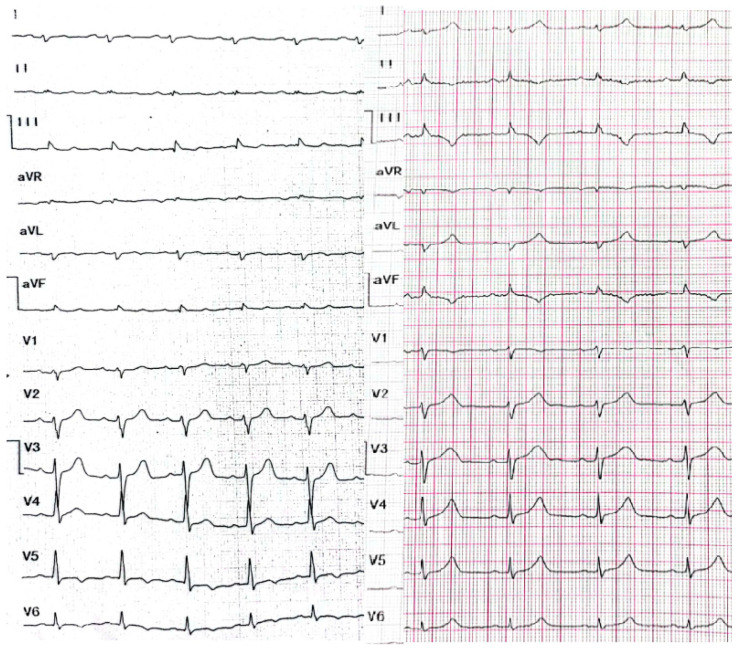

A 29-year-old male patient, a manual worker without history of overt infectious myocarditis, without classic risk factors for cardiovascular diseases, with mixed anxiety and depressive disorder, was treated with prescribed off-label medical marijuana (delta-9-tetrahydrocannabinol THC 19% and cannabidiol CBD < 1%, bred from Lemon Skunk Cannabis Strain in the form of unprocessed dried leaves) for around 3 years, smoked at least 3–4 times a day and was diagnosed with severe cannabis use disorder (continued use of cannabis despite clinically significant impairment) [ref. 6]. It was diagnosed by a psychiatrist according to the fifth version of the Diagnostic and Statistical Manual of Mental Disorders (DSM-5) with 8 out of 11 criteria met: hazardous use, social/interpersonal problems, neglected major roles, withdrawal, used larger amounts/longer, much time spent using, activities given up and craving [ref. 7]. Moreover, the patient was categorized as a chronic user [ref. 8]. He had been suffering from paroxysmal hemodynamically unstable ventricular tachycardia (VT). The first episode occurred 30 months ago and the patient was referred from an emergency room to a distant cardiology center, where upon coronarography, apart from myocardial bridge localized in the middle segment of the left anterior descending coronary artery no lesions in the coronary arteries were recorded. There were no specific abnormalities recognized in resting ECG (Figure 1, left panel). In the echocardiogram the structure and function of the heart was normal, apart from a mildly compromised left ventricular systolic function with left ventricular ejection fraction (LVEF) of 43%. At that time the patient did not consent to the proposed diagnostics of VT consisting of cardiovascular magnetic resonance imaging of the heart, electrophysiological study, genetic testing and therapy with subcutaneous implantable cardioverter-defibrillator. He received metoprolol in extended-release drug formulation (metoprolol succinate) of 25 mg q.d. due to intolerance of higher doses, potassium, magnesium and vitamin B6 supplementation. Within this period, the subject experienced at least six episodes of VT that required medical assistance. Moreover, 7 months earlier he was admitted to the catheterization unit again after an acute episode of retrosternal pain following marijuana intake. Once more, no lesions within the coronary arteries were observed in coronarography (Figure 2 and Figure 3). ECG showed no signs of ischemia, echocardiography was without segmental dysfunction of cardiac muscle, and LVEF equaled 40%. Noteworthy, the top troponin T serum concentration exceeded the upper end of the scale (>10,000 ng/mL), with CPK of 4167 U/L, CK-MB-428 U/L and CRP 3.4 mg/L. Non-ST-elevation myocardial infarction was diagnosed but the patient still declined extended diagnostics and marijuana addiction therapy. The treatment was supplemented with acetylsalicylic acid 75 mg q.d., clopidogrel 75 mg q.d., ramipril 1.25 mg q.d., rosuvastatin 10 mg q.d., eplerenone 25 mg q.d. and pantoprazole 20 mg q.d.

This time the individual was admitted to our cardiology center after another episode of VT, with cardiac arrest in the mechanism of VT at an emergency room (VT score—4 points, positive result of the Vereckei, Brugada and limb algorithms for the diagnosis of VT on ECG, Figure 4) treated with electrical cardioversion for further treatment [ref. 9,ref. 10]. The physical examination showed no significant abnormalities, the patient’s weight was 69 kg, height—190 cm, body mass index–BMI–19.11 kg/m2. Peripheral blood saturation—96%, body temperature—36.7 degrees C. Blood pressure was in the range of 100–110/60–70 mm Hg. In laboratory tests: white blood cells count—WBC—8.45 K/µL; hemoglobin—Hgb—13.3 g/dL; platelets count—PLT—260 K/µL; troponin T—317.6 ng/mL (norm < 30); N-terminal pro-brain natriuretic peptide—NT-proBNP—905 pg/mL; creatine phosphokinase—CPK—352 U/L; MB iso-enzyme of creatine kinase-CK-MB-24 U/L (6.8% CPK); thyroid-stimulating hormone—TSH—0.805 µU/mL; total cholesterol—2.6 mmol/L; low-density lipoprotein cholesterol—LDL—1.35 mmol/L; high-density lipoprotein cholesterol—HDL—0.89 mmol/L; triglycerydes—TG—0.87 mmol/L; glucose—5.6 mmol/L; creatinine—77 µmol/L (estimated glomerular filtration rate—eGFR > 90 mL/1.73 m2/min); sodium—141 mmol/L; potassium—3.61 mmol/L; chlorides—102 mmol/L; C-reactive protein—CRP—1.0 mg/L; d-dimer—413 ng/mL; alcohol—0.2 per mille; international normalized ratio- INR—1.23; activated partial thromboplastin time—aPTT—34 s; Abbott antigen test for SARS-CoV-2 virus negative; PCR test for COVID-19 also negative. The resting electrocardiogram revealed a sinus rhythm of 76 beats/min, the axis of the heart inclined moderately to the right, low voltage of QRS complexes in the limb leads, negative T waves in V5 and V6, and positive–negative in aVL. PQ equaled 160 ms, QRS—90 ms, QTc—440 ms (Figure 1, right panel). On echocardiography, the left ventricle was not enlarged (its end-diastolic dimension—55 mm), the interventricular septum was moderately thickened (11 mm in the diastolic phase), normal left ventricular systolic function was observed, with no segmental abnormalities of contractility (left ventricular ejection fraction—LVEF was 55%). No other significant abnormalities, including significant valve defects, were observed.